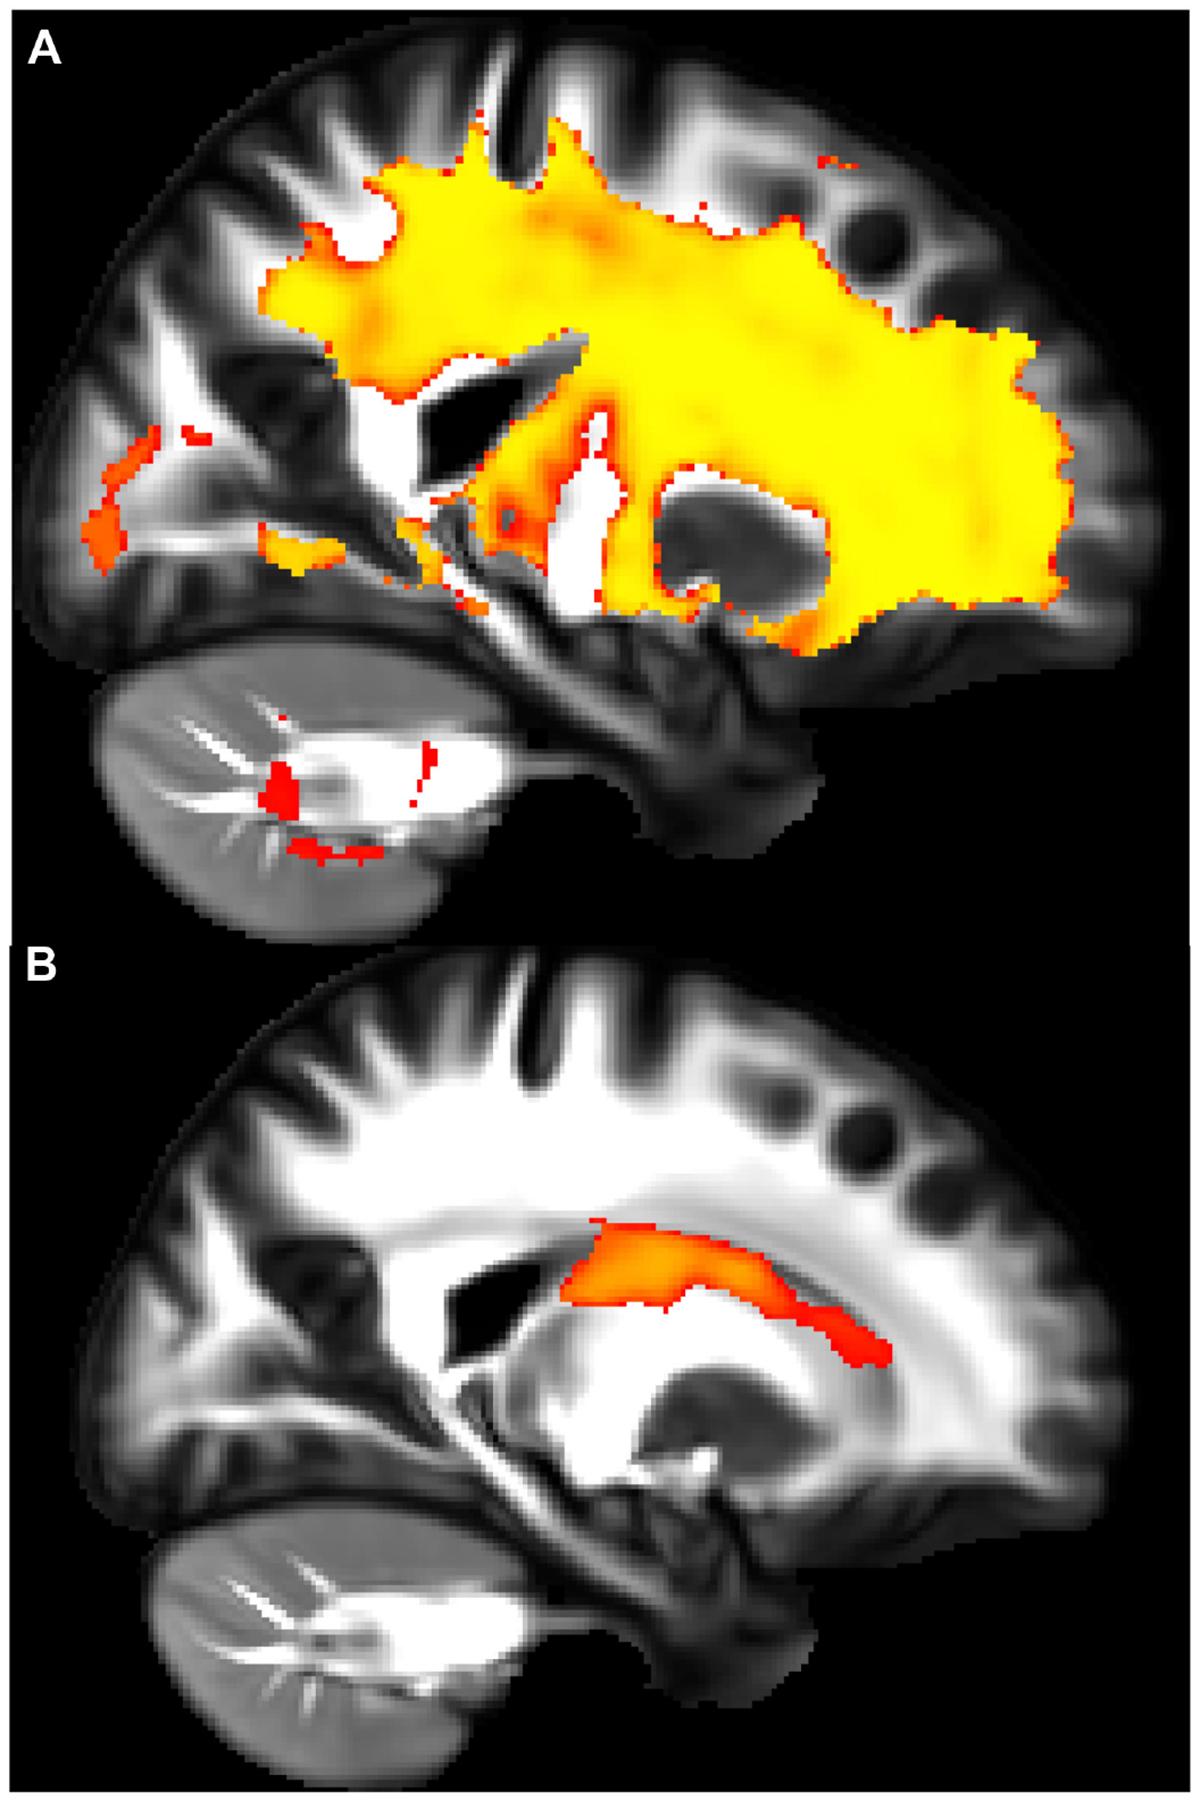

Glucagon-like peptide-1 (GLP-1) is a hormone that regulates blood glucose levels and is produced by the enteroendocrine glands in the large and small intestines in response to the consumption of foods that contain carbohydrates, fats, and proteins. When GLP-1 is secreted, it acts on the pancreas to increase insulin production and secretion, while decreasing pancreatic glucagon secretion in order to lower serum glucose. However, GLP-1 also regulates metabolism through the gut-brain axis. While GLP-1 is primarily produced in the gut and released into the bloodstream, small quantities of it can also be synthesized in distinct areas of neurons located in the hindbrain. Recent studies have proposed that GLP-1 receptor (GLP-1R) agonists (GLP-1RAs) may protect against neuroinflammatory diseases. GLP-1RAs may also be a therapeutic target for asthma as animal models show that these drugs reduce allergen-induced airway inflammation, as the GLP-1R is expressed on lung epithelial and endothelial cells. There is a notable association between insulin resistance and the onset of asthma, particularly among obese people, with this association suggesting that metabolic dysfunction may play a role in asthma development. There is also evidence that there may be a link between asthma pathobiology and neuroinflammation, suggesting that GLP-1 and its analogs may regulate neuroinflammatory pathways that contribute to asthma pathogenesis. Interest is growing, though research remains limited, in how inflammation in the nervous system and lung might be linked. This review will explore how GLP-1R signaling could inhibit interdependent inflammation in both the lung and nervous system. This review will first focus on the inflammation that is known to exist in asthma, then pivot to the current state of neural regulation of asthma, and finally speculate on how GLP-1RA signaling could inhibit both neural and lung inflammation in asthma treatment.